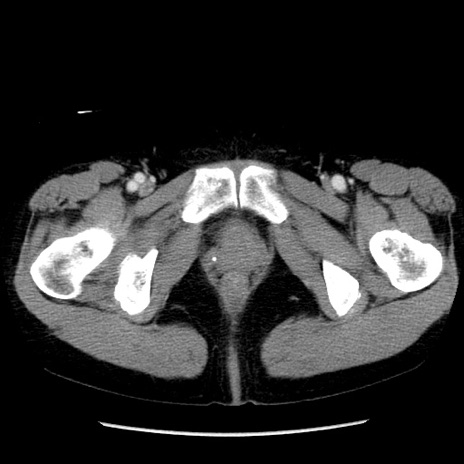

症例6(横断像)

【症例】50歳代女性

【主訴】下腹部痛

【現病歴】本日朝より下痢2回あり。 昼食を食べた後、嘔吐3回、下腹部痛認め、症状軽快せず、当院救急搬送。

最終食事:本日昼(生ものなし)。 昨日の夜、刺身を食ぺたとのこと。周囲に同様の症状の者なし。普段、排便は毎日あるとのこと。

【既往歴】卵巣癌術後(8年前に当院で卵巣摘出)

【身体所見】 意識清明、腹部:平坦、腸蠕動音→、やや硬、下腹部自発痛・圧痛あり、反跳痛あり、筋性防御なし。

【データ】WBC 16000、CRP 0.01